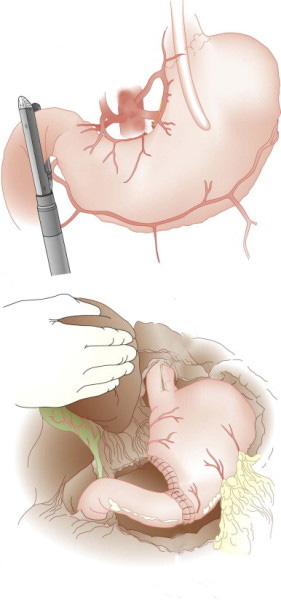

Passagem de Balão Intragástrico

1. O balão intragástrico é introduzido desinsuflado durante a endoscopia e colocado no estômago.

2. Um líquido azul (azul de metileno diluído em soro fisiológico) é colocado dentro do balão através de uma válvula. O volume varia entre 500-700 ml.

3. O aparelho de endoscopia é removido e o balão intragástrico pode ser deixado por um período de até 6 meses.

Como funciona o balão intragástrico?

O balão intragástrico ocupa um espaço dentro do estômago e o paciente fica com sensação de plenitude e saciedade precoce. Em outras palavras, sobra menos espaço para os alimentos, diminuindo o volume ingerido nas refeições.

Passagem de Balão Intragástrico

1. O balão intragástrico é introduzido desinsuflado durante a endoscopia e colocado no estômago.

2. Um líquido azul (azul de metileno diluído em soro fisiológico) é colocado dentro do balão através de uma válvula. O volume varia entre 500-700 ml.

3. O aparelho de endoscopia é removido e o balão intragástrico pode ser deixado por um período de até 6 meses.

Como funciona o balão intragástrico?

O balão intragástrico ocupa um espaço dentro do estômago e o paciente fica com sensação de plenitude e saciedade precoce. Em outras palavras, sobra menos espaço para os alimentos, diminuindo o volume ingerido nas refeições.